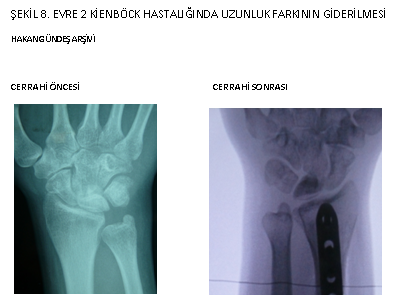

Erken evrelerde ön kol kemiklerindeki uzunluk farkı giderilerek (uzun olan radyus kısaltılarak) Lunatumun üzerindeki basınç azaltılır ve ezilmesi önlenir (şekil 8 ve 9). Bu yöntemin en büyük avantajlarından birisi, el bileği eklemine girişim yapılmadığı için cerrahi sonrası eklem sertliği gözlenmemesidir. Bazı kişilerde Kienböck hastalığı gözlenmesine karşın önkol kemiğinde (ulna) kısalık yoktur.